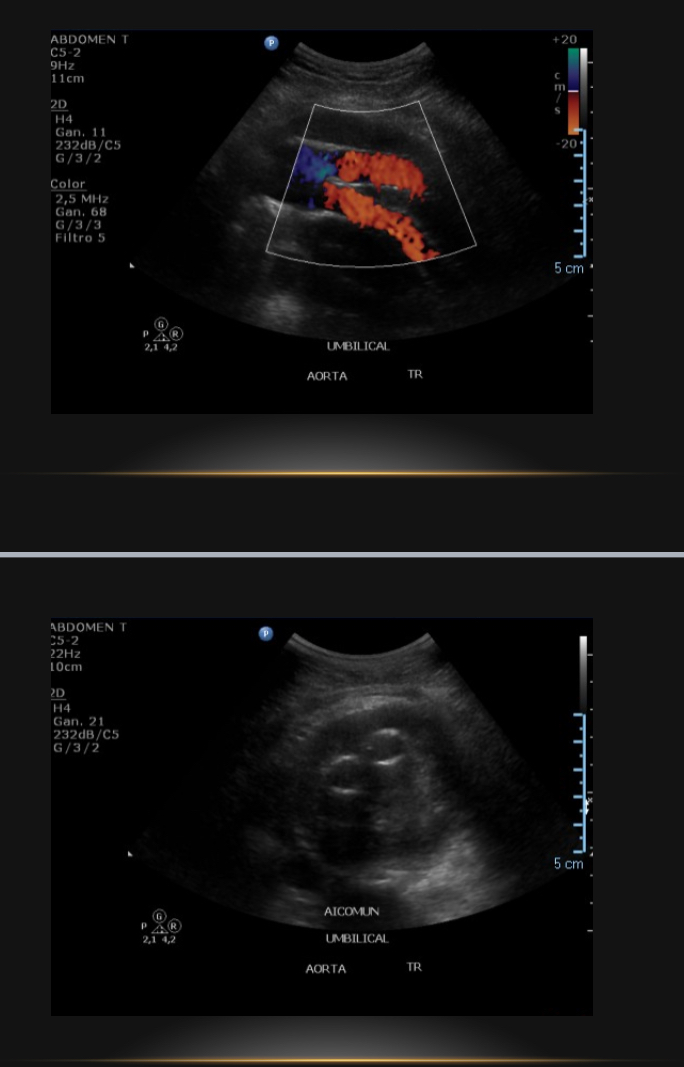

Endoprótesis aortoiliaca

Grandes vasos